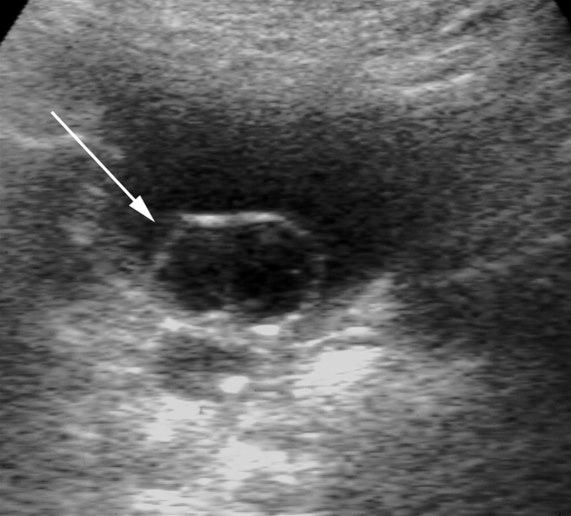

Ureterocele

Ureterocele (UL)

Sekkformet utposning ved ureterostiet (pil)